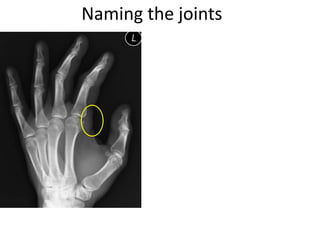

This document provides an overview of hand anatomy including:

- Naming the bones, joints, tendons, nerves and skin landmarks of the hand and wrist.